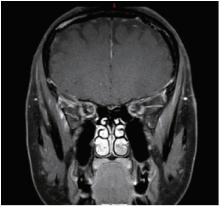

Figure 3

Orbital magnetic resonance imaging of optic perineuritis in sarcoidosis Orbital magnetic resonance imaging shows enhancement of the sheath in the posterior intraorbital segment and intracanalicular segment of the left optic nerve."